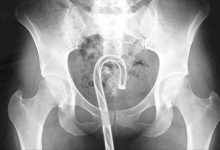

小时候拿东西就往嘴里塞...那是不懂事,但是长大了就不会这幺做了吗?这就不好说了,国外一个消费者製品安全委员会就做了一项统计,2019年在美国因异物急诊的案件,它们统计了一下发现其实相关案例层出不穷,一年之内在美国发生的案例数不清,不管是男...